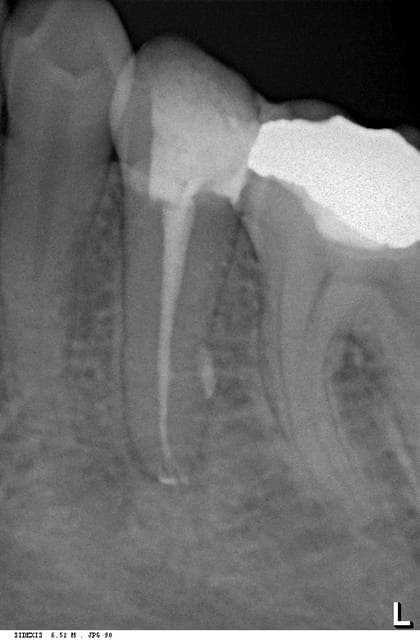

pour la radio, j'ai utilisé une lime 10, puis uniquement l'isiendo jusqu'à l'apex après avoir bien sûr utiliser le localisateur sous dige pour déterminer ma LT.

Pour le ciment j'utilise du sealite + revo condensor c 'est vrai que ca a fusé épais dans le péri-apex.

Je n'ai plus d'appréhension à aller à la LT direct avec ces limes là, j'ai fait plus d'une trentaine de bio je n'ai pas eu de casse même sur les canaux compliqués.